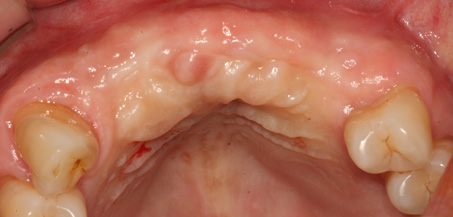

상악동 거상술

상악동 거상술 고난이도 뼈이식술 입니다.

청담네오플란트에서는 상악동 거상술을 비롯한

고난이도 임플란트 시술 노하우가 풍부한 치의학 박사

전문의가 직접 상악동 거상술을 시행합니다

상악동은 윗턱뼈 내부의 구조물로서 개개인에 따라 생김새가 다릅니다.

상악동의 바닥이 잇몸뼈 방향으로 많이 내려온 경우, 임플란트를 식립하기에

잇몸뼈가 부족하게 됩니다. 이러한 경우 상악동 내부로 뼈이식을 하는

상악동 거상술이 필요하게 됩니다.

B

A